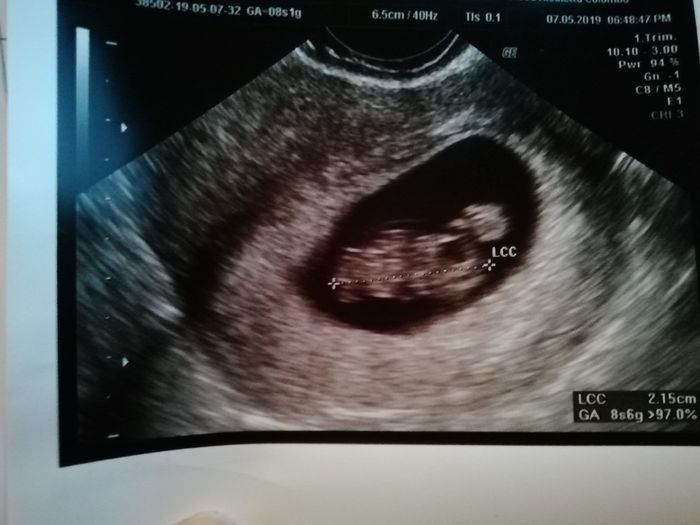

Ragazze... inizio per dirvi che non è mia L ecografia... ma ve lo chiedo per conto di terzi 😊 siamo a 6+4 prima ecografia interna.... secondo voi cosa è?! Secondo me è maschio ma chiedo a voi esperti un parere... grazie mille a chi mi aiuterà 💕♥️